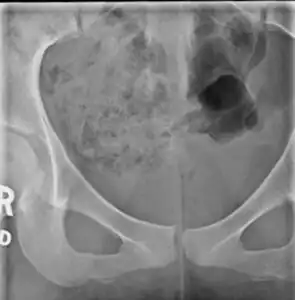

X-ray

Lateral radiograph showing a fracture of the coccyx, as well as a lower lumbar fracture